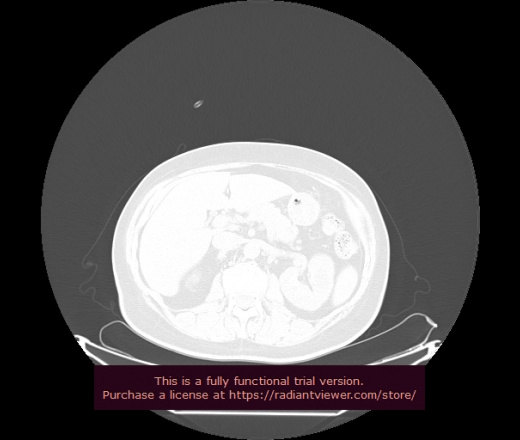

Уважаемые коллеги, если имеется интерес, сможете ли Вы спрогнозировать дальнейшее +-одинаковое течение процесса у 4 данных разных пациентов? Зацепиться где-то можно очень просто, где-то нельзя.